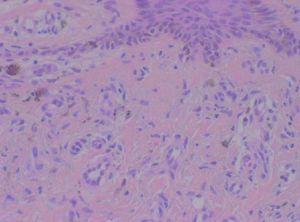

Se realizaron dos biopsias con un intervalo de un año, y ambas mostraban cambios similares, consistentes en neoformación de vasos en la dermis papilar y media, unos de morfología capilar y otros en forma de hendidura (fig. 2). Las células endoteliales que tapizaban los vasos no mostraban atipias y existía una extravasación de eritrocitos y macrófagos, con depósitos de hemosiderina en la dermis e infiltrado inflamatorio de linfocitos, histiocitos, eosinófilos y algunas células plasmáticas (fig. 3). El CD34 fue positivo en las células endoteliales, pero negativo en las células perivasculares. La expresión de ADN del herpesvirus 8 humano (HHV-8) fue negativa.

Figura 2. Neoformación de vasos en dermis papilar y media, unos con morfología capilar y otros con forma de hendidura. Hematoxilina-eosina, x40.